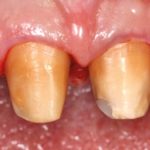

Valutazione clinica della risposta dei tessuti gengivali alla tecnica BOPT

Clinical evaluation of the gingival tissues response to BOPT technique La tecnica BOPT può fornire una valida alternativa alla chirurgia parodontale nella correzione di lievi...